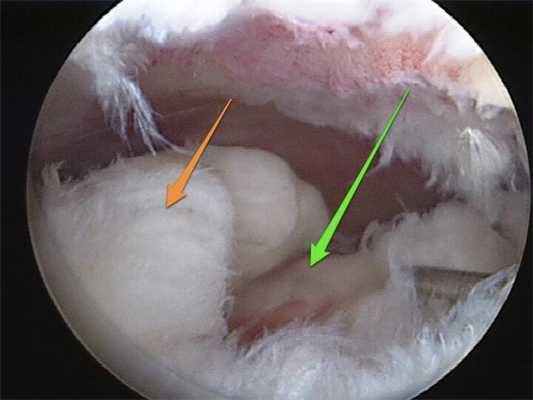

Изображение полости сустава.

В целях высокоинформативной диагностики специалист через микропортал вводит рабочую трубку устройства внутрь сустава, в которую вмонтированы система ультрасильных линз, мощный световой источник и видеозаписывающая цифровая техника. Все структуры, что «видит» артроскоп, визуализируются на экране в «живом» виде, причем изображение поступает в многократно увеличенном формате. Врач может найти точное расположение травмы или дегенеративных изменений, установить характер патологии, степень тяжести и принять меры.

Доказано, что артроскопия превосходит любые существующие способы диагностики. Она четко показывает изнутри все структурные единицы костного соединения в самых мельчайших подробностях, позволяет определить даже мелкие скрытые повреждения, которые нельзя выявить при помощи стандартной рентгеноскопии или артрографии, ультразвука, МРТ, КТ и прочих популярных методов визуализации.

Метод используется не только как средство диагностики, но и в качестве лечебно-восстановительной тактики. Обнаружив те или иные нарушения хрящевой поверхности, доктор может сразу же их ликвидировать. Оперативные манипуляции он выполнит через дополнительный разрез (размер около 6 мм) с использованием микрохирургических инструментов, при этом весь процесс он будет совершать, глядя на монитор.